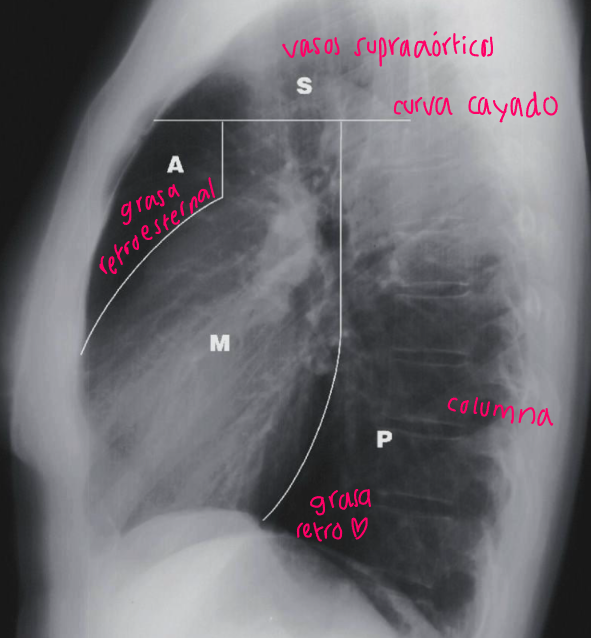

7

Q

Esta es una radiografía de:

A

Mediastino